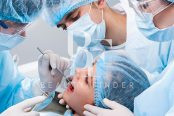

The Dental and Maxillofacial Clinic at Dr. Soliman Fakeeh Hospital in Riyadh provides high-quality dental services tailored to meet the diverse needs of patients. This clinic is known for its specialized dental treatments and advanced technologies, ensuring that patients receive comprehensive and personalized care. The clinic’s expert team consists of highly trained dental professionals who are committed to delivering the best possible outcomes, making it a trusted choice for dental care in Riyadh.

- Oral and Maxillofacial Surgery:

- Expertise in wisdom tooth removal, dental implants, and jaw surgeries.

- Cosmetic facial surgery and laser dentistry for a variety of oral health concerns.

- Specialized care for complex facial and dental conditions.

- Expert Care: Patients trust the clinic for its experienced dental team and high standards of treatment.

- State-of-the-Art Facility: Equipped with the latest technology, the clinic offers accurate diagnosis and effective treatments.